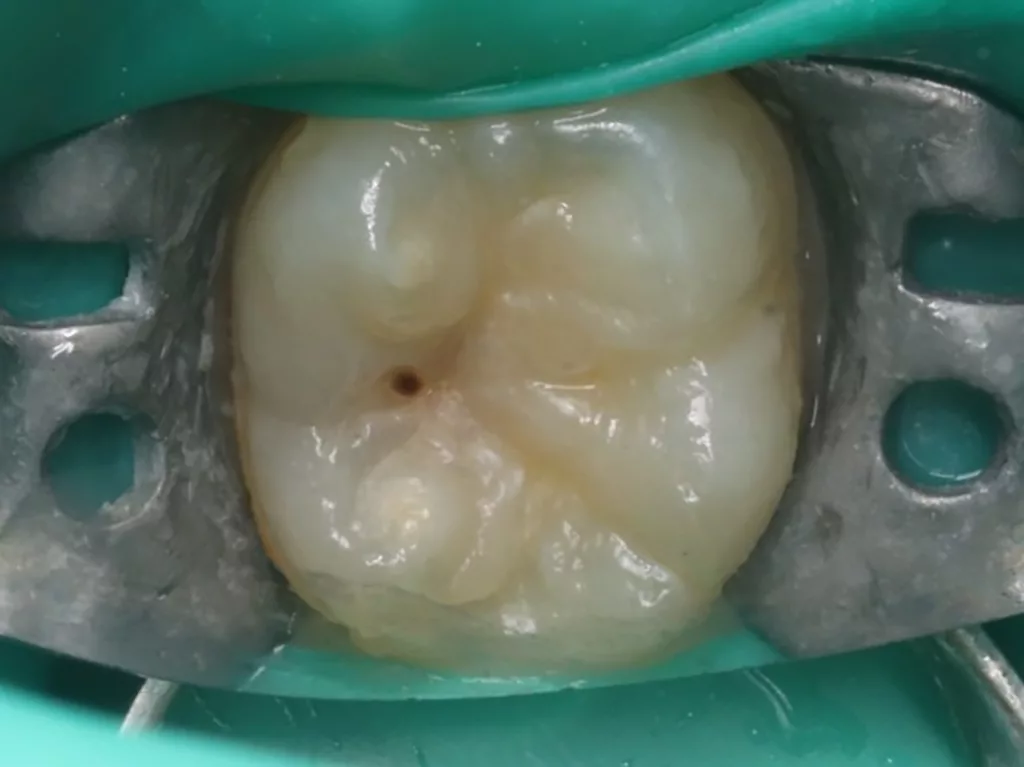

Das siebenjährige Mädchen wurde von einer Kollegin zur Behandlung einer atypischen intrakoronalen Aufhellung im Kronenbereich des nach Durchbruch befindlichen symptomatischen Zahnes 46 überwiesen (Abb. 20). Anamnestisch bestanden seit zwei Tagen kurzintervallige Spontan- und Nachtschmerzen, die mit Ibuprofen 40 mg/ml Kindersirup behandelt wurden. Das Röntgenbild zeigte einen umfangreichen runden Dentindefekt unter intaktem Zahnschmelz, der bis in das Pulpakavum reichte. Daraus ergab sich die Verdachtsdiagnose PEIR des Zahnes 46 (Grad 3 der Läsion nach Seow) in Kombination mit einer akuten Pulpitis. Nach Leitungsanästhesie am Foramen mandibulae mit Septanest 1/100 000 (Septodont, Frankreich) und STA-System (Milstone Scientific, USA) konnte der Zahn mithilfe von Kofferdam (Klammer U67, KSK Dentech, Japan) gut isoliert werden (Abb. 21). Um die ursprüngliche Zahnanatomie zu imitieren, wurde ein Okklusalstempel aus dem flüssigen Kofferdam OpalDam (Ultradent, Frankreich) und einem Microbrushapplikator angefertigt.

Der PEIR-Defekt schimmerte unter der lingualen Querfissur deutlich dunkler durch (Abb. 21), sodass die Entscheidung getroffen wurde, den Defekt an genau dieser Stelle zu eröffnen (Abb. 22). Das resorbierte intrakoronale Weichgewebe, das die Läsion nur zum Teil füllte, konnte dann gut visualisiert werden (Abb. 22). Kariös verändertes Dentin wurde nicht gefunden. Nach Eröffnung des Pulpahorns sah die Pulpa blass und avaskulär mit Anzeichen einer geringen Blutung aus (Abb. 23). Die komplette Kronenpulpa wurde bis zur Höhe der Kanaleingänge mit einem runden Diamantbohrer unter Wasserkühlung entfernt. Vor und nach der Prozedur wurde die Läsion zuerst mit 1%igem NaOCl und anschließend mit physiologischer Kochsalzlösung gespült. Die Blutung stoppte innerhalb von zwei Minuten vollständig, die Wurzelpulpa erschien gesund, regulär vaskularisiert und sauber (Abb. 24). Es wurde eine reversible Pulpitis diagnostiziert. Die Abdeckung der Wurzelpulpa erfolgte mit einem hydraulischen Kalziumsilikatzement (Rootdent, Technodent), der mit dem Glasionomerzement Fuji II LC (GC, Japan) als temporäre Füllung abgedeckt wurde. Die Platzierung des MTA-Zements wurde abschließend mittels einer Röntgenaufnahme überprüft (Abb. 27). Nach zwei Wochen war die junge Patientin komplett beschwerdefrei. Unter erneuter Trockenlegung mit Kofferdam wurde die adhäsive koronale Restauration mit Komposit Estelite ASTERIA OCE, A2B und Universal Flow AO2 (Tokuyama, Japan) mithilfe eines vorab angefertigten Okklusalstempels erstellt (Abb. 25 und 26). Ein Jahr später kam die Patientin beschwerdefrei zur Nachkontrolle. Das Röntgenbild (Abb. 28) zeigte keinen pathologischen Befund sowie eine physiologische Weiterentwicklung des Wurzelwachstums in Länge und Dicke der Wurzelwände.